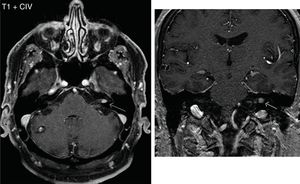

Reading of the protocolsIn the reading made by the neuroradiologist of the studies without IVC, he found no alteration in 32% of the studies, and documented 17.5% of pathology of the ear and 50% of extraotic pathology (Fig. 3). On the other hand, in the reading of the protocols with IVC, there were no substantial changes when comparing the results with the reading of the protocols without IVC. He found 22.5% of otic pathology with the same diagnostic spectrum as the protocol without IVC, plus two post-surgical changes after mastoidectomies, one with tumor remnant and one without tumor remnant.

The pathology identified in the ear was schwannomas (Fig. 4), labyrinthitis ossificans, suspicion of retrofenestral otosclerosis, cholesteatoma and semicircular canal dysplasia. Among the extraotic pathology found, in addition to the cavernoma shown in Fig. 4, a low-grade glioma in the cerebellar vermis and a control of a temporobasal brain abscess already practically in resolution stand out (Fig. 5), as well as other alterations of less relevance (ischemic lesions in the brain parenchyma, inflammatory sinusopathy, etc.).

DiscussionWhen reading the protocols without and with gadolinium, no striking differences were found in the results obtained by the neuroradiologist, because in the protocol without IVC a 17.5% specific pathology of ears was found compared to 22.5% after administering IVC. The pathology that was found was very similar, adding only in the protocols with IVC the finding of two patients with mastoidectomies. It is important to note that the FLAIR sequence is acquired with fat suppression and it is difficult to assess bone structures, while in the post-contract sequences one of the 3D sequences is acquired without fat suppression, which allows better evaluation of bone structures and therefore the mastoid. If a protocol is sought to be conducted without contrast, this issue should be taken into account, and a 3D-T1 weighted MRI without fat suppression for mastoid assessment should be considered.